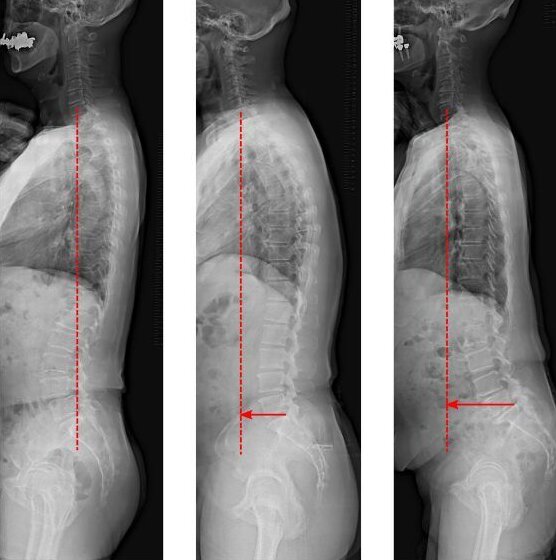

به نقل از سایتک دیلی، این پرسش که آیا کاهش شناختی ممکن است با ارزیابی تعادل ستون فقرات شناسایی شود یا خیر، از طریق یک آزمایش در مقیاس بزرگ مورد بررسی قرار گرفت که در افراد بین ۵۰ تا ۸۹ سال انجام شد. پژوهشگران “دانشگاه شینشو”(Shinshu University) ژاپن، ارتباطی را بین “محور عمودی ساژیتال”(SVA) و افزایش سن و کاهش عملکرد شناختی کشف کردند.

پژوهشگران دریافتند که هنگام مشاهده بدن از پهلو، هرچه سر و گردن بیشتر جلو بیایند، احتمال بیشتری وجود دارد که نشانههای زوال شناختی در بیماران مشاهده شود. در مردان، محور عمودی ساژیتال با کاهش شناختی مستقل از افزایش سن مرتبط بود. کاهش شناختی در زنان صرف نظر از سن، شایعتر بود.

برای بررسی انبوه این موضوع، افراد مسن ساکن شهر اوبوسه، ناگانو مورد ارزیابی قرار گرفتند. این بررسی نشان داد که در افراد مسن ژاپنی، کسانی که قدامی شدن ستون فقرات را نشان میدهند، بیشتر در معرض کاهش عملکرد شناختی قرار دارند. زوال شناختی با ترکیب سن و میزان عدم تعادل ستون فقرات، به صورت قابل اطمینانی تشخیص داده شد.